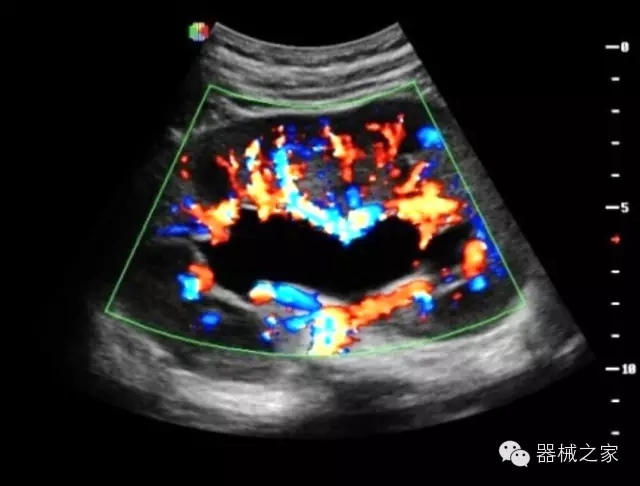

經(jīng)典產(chǎn)品:S8EXP

臨床圖片賞析

產(chǎn)品特點(diǎn)

優(yōu)異的成像技術(shù)

·亞陣元技術(shù):獨(dú)有的亞陣元技術(shù),對獨(dú)立晶片做二次切割,減少旁瓣偽像,增加臨床診斷的準(zhǔn)確性;

·μ-Scan微米成像技術(shù):開立獨(dú)有的μ-Scan技術(shù),還原出真實(shí)細(xì)膩、層次對比優(yōu)異的二維圖像;

·倒相諧波成像技術(shù):倒相諧波技術(shù)在去除基波信號的基礎(chǔ)上獲取兩倍二次諧波信號,提高組織圖像的對比分辨力;

·智能微血流成像技術(shù):智能微血流捕捉技術(shù)可以提取出隱藏在背景噪聲中的弱血流信號,大大提高低速血流的敏感性;

全面的臨床解決方案

超聲科常規(guī)領(lǐng)域應(yīng)用

·移植S40高端臺式彩超高端平臺技術(shù),滿足超聲科腹部、淺表、婦產(chǎn)科、心血管、肌骨等應(yīng)用,提供超聲科完美解決方案;

·實(shí)時的彈性成像技術(shù):提高了小器管(乳腺,甲狀腺、淺表軟組織腫瘤等)疾病鑒別診斷;

·IMT血管內(nèi)中膜自動測量:為血管性疾病評估提供了有效的評估手段;

·心功能綜合指數(shù)(TEI指數(shù)):用于左、右心室整體心臟收縮舒張功能評估的測量方法;

·全方位可調(diào)M型:有利于更好的觀察心腔大小及室壁階段性運(yùn)動的異常情況;

·組織多普勒成像(TDI):TDI可定量評價心肌運(yùn)動,判斷是否有局部病變,還可評價早期的舒張功能;

·高效3D/4D成像技術(shù):高速的4D幀頻,豐富的3D成像模式,智能斷層切片功能;

POC領(lǐng)域解決方案

·外觀小巧;

·穿刺增強(qiáng)技術(shù):可有效提高進(jìn)針區(qū)圖像分辨率,提高進(jìn)針亮度,全面提高一次性穿刺的成功率;

全面的術(shù)中探頭解決方案

·小凸探頭:開放性手術(shù),實(shí)時監(jiān)測病灶位置,提高手術(shù)成功率,可應(yīng)用于麻醉科、肝膽外科、腫瘤外科、神經(jīng)外科、泌尿外科等手術(shù);

·L型線陣探頭:高分辨率圖像,清晰顯示病灶位置,提高手術(shù)成功率,可應(yīng)用于麻醉科、胸外科、肝膽外科、腫瘤外科、神經(jīng)外科、泌尿外科等應(yīng)用;

·MPTEE:經(jīng)食道探頭術(shù)中監(jiān)測,可測量心臟前負(fù)荷(左室舒張末期大小、右房大?。?、心排血量、后負(fù)荷、收縮功能、室壁運(yùn)動分析、肝靜脈血流(與中心靜脈壓相關(guān))等,術(shù)后還能及時評估手術(shù)效果評估;

·獨(dú)有的大角度及實(shí)時溫控技術(shù),能同一切面顯示宮頸及宮體,有效減低了患者的痛苦,及保護(hù)粘膜保證了醫(yī)療安全;

高效的人機(jī)工程學(xué)設(shè)計(jì)

·15‘’高清醫(yī)用顯示器;

·內(nèi)置雙探頭接口;

·可升降臺車,1拖3探頭擴(kuò)展器;

·m-Tuning一鍵優(yōu)化;